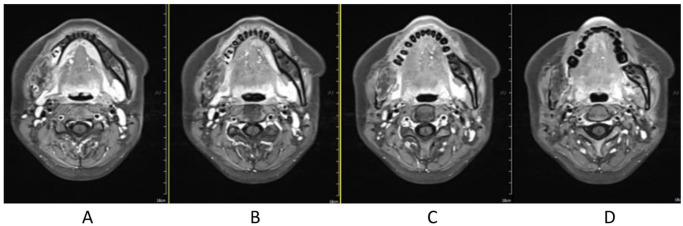

复发性成釉细胞瘤的碳离子放射治疗:一例报告

Carbon ion radiotherapy for recurrent ameloblastoma: A case report.

Ameloblastoma is a kind of benign, odontogenic tumor of epithelial origin, and surgery is mainstay treatment method; however, recurrence is common, and usually the treatment for recurrence is still surgery. We report on a patient of recurrent ameloblastoma treated with carbon ion radiation therapy and achieved a good efficacy. A 25-year-old female with relapse of an ameloblastoma was referred to the Wuwei Heavy Ion Center for carbon ion therapy. She had been initially diagnosed with ameloblastoma 8 years ago and underwent operation of right mandible ameloblastoma. After she transferred to our center, she accepted a dose of 60 GyE carbon ion radiation therapy, and the efficacy is good. Carbon ion radiation therapy can be an effective treatment option for ameloblastoma.

摘要

成釉细胞瘤是一种起源于上皮的良性牙源性肿瘤,手术是主要的治疗方法;然而,复发很常见,通常复发后的治疗仍然是手术。我们报告了一例接受碳离子放射治疗并取得良好疗效的复发性成釉细胞瘤患者。一名25岁复发性成釉细胞瘤女性患者被转诊至武威重离子中心接受碳离子治疗。她8年前最初被诊断为成釉细胞瘤,并接受了右下颌骨成釉细胞瘤手术。转至我们中心后,她接受了60GyE的碳离子放射治疗,疗效良好。碳离子放射治疗可以成为成釉细胞瘤的一种有效治疗选择。